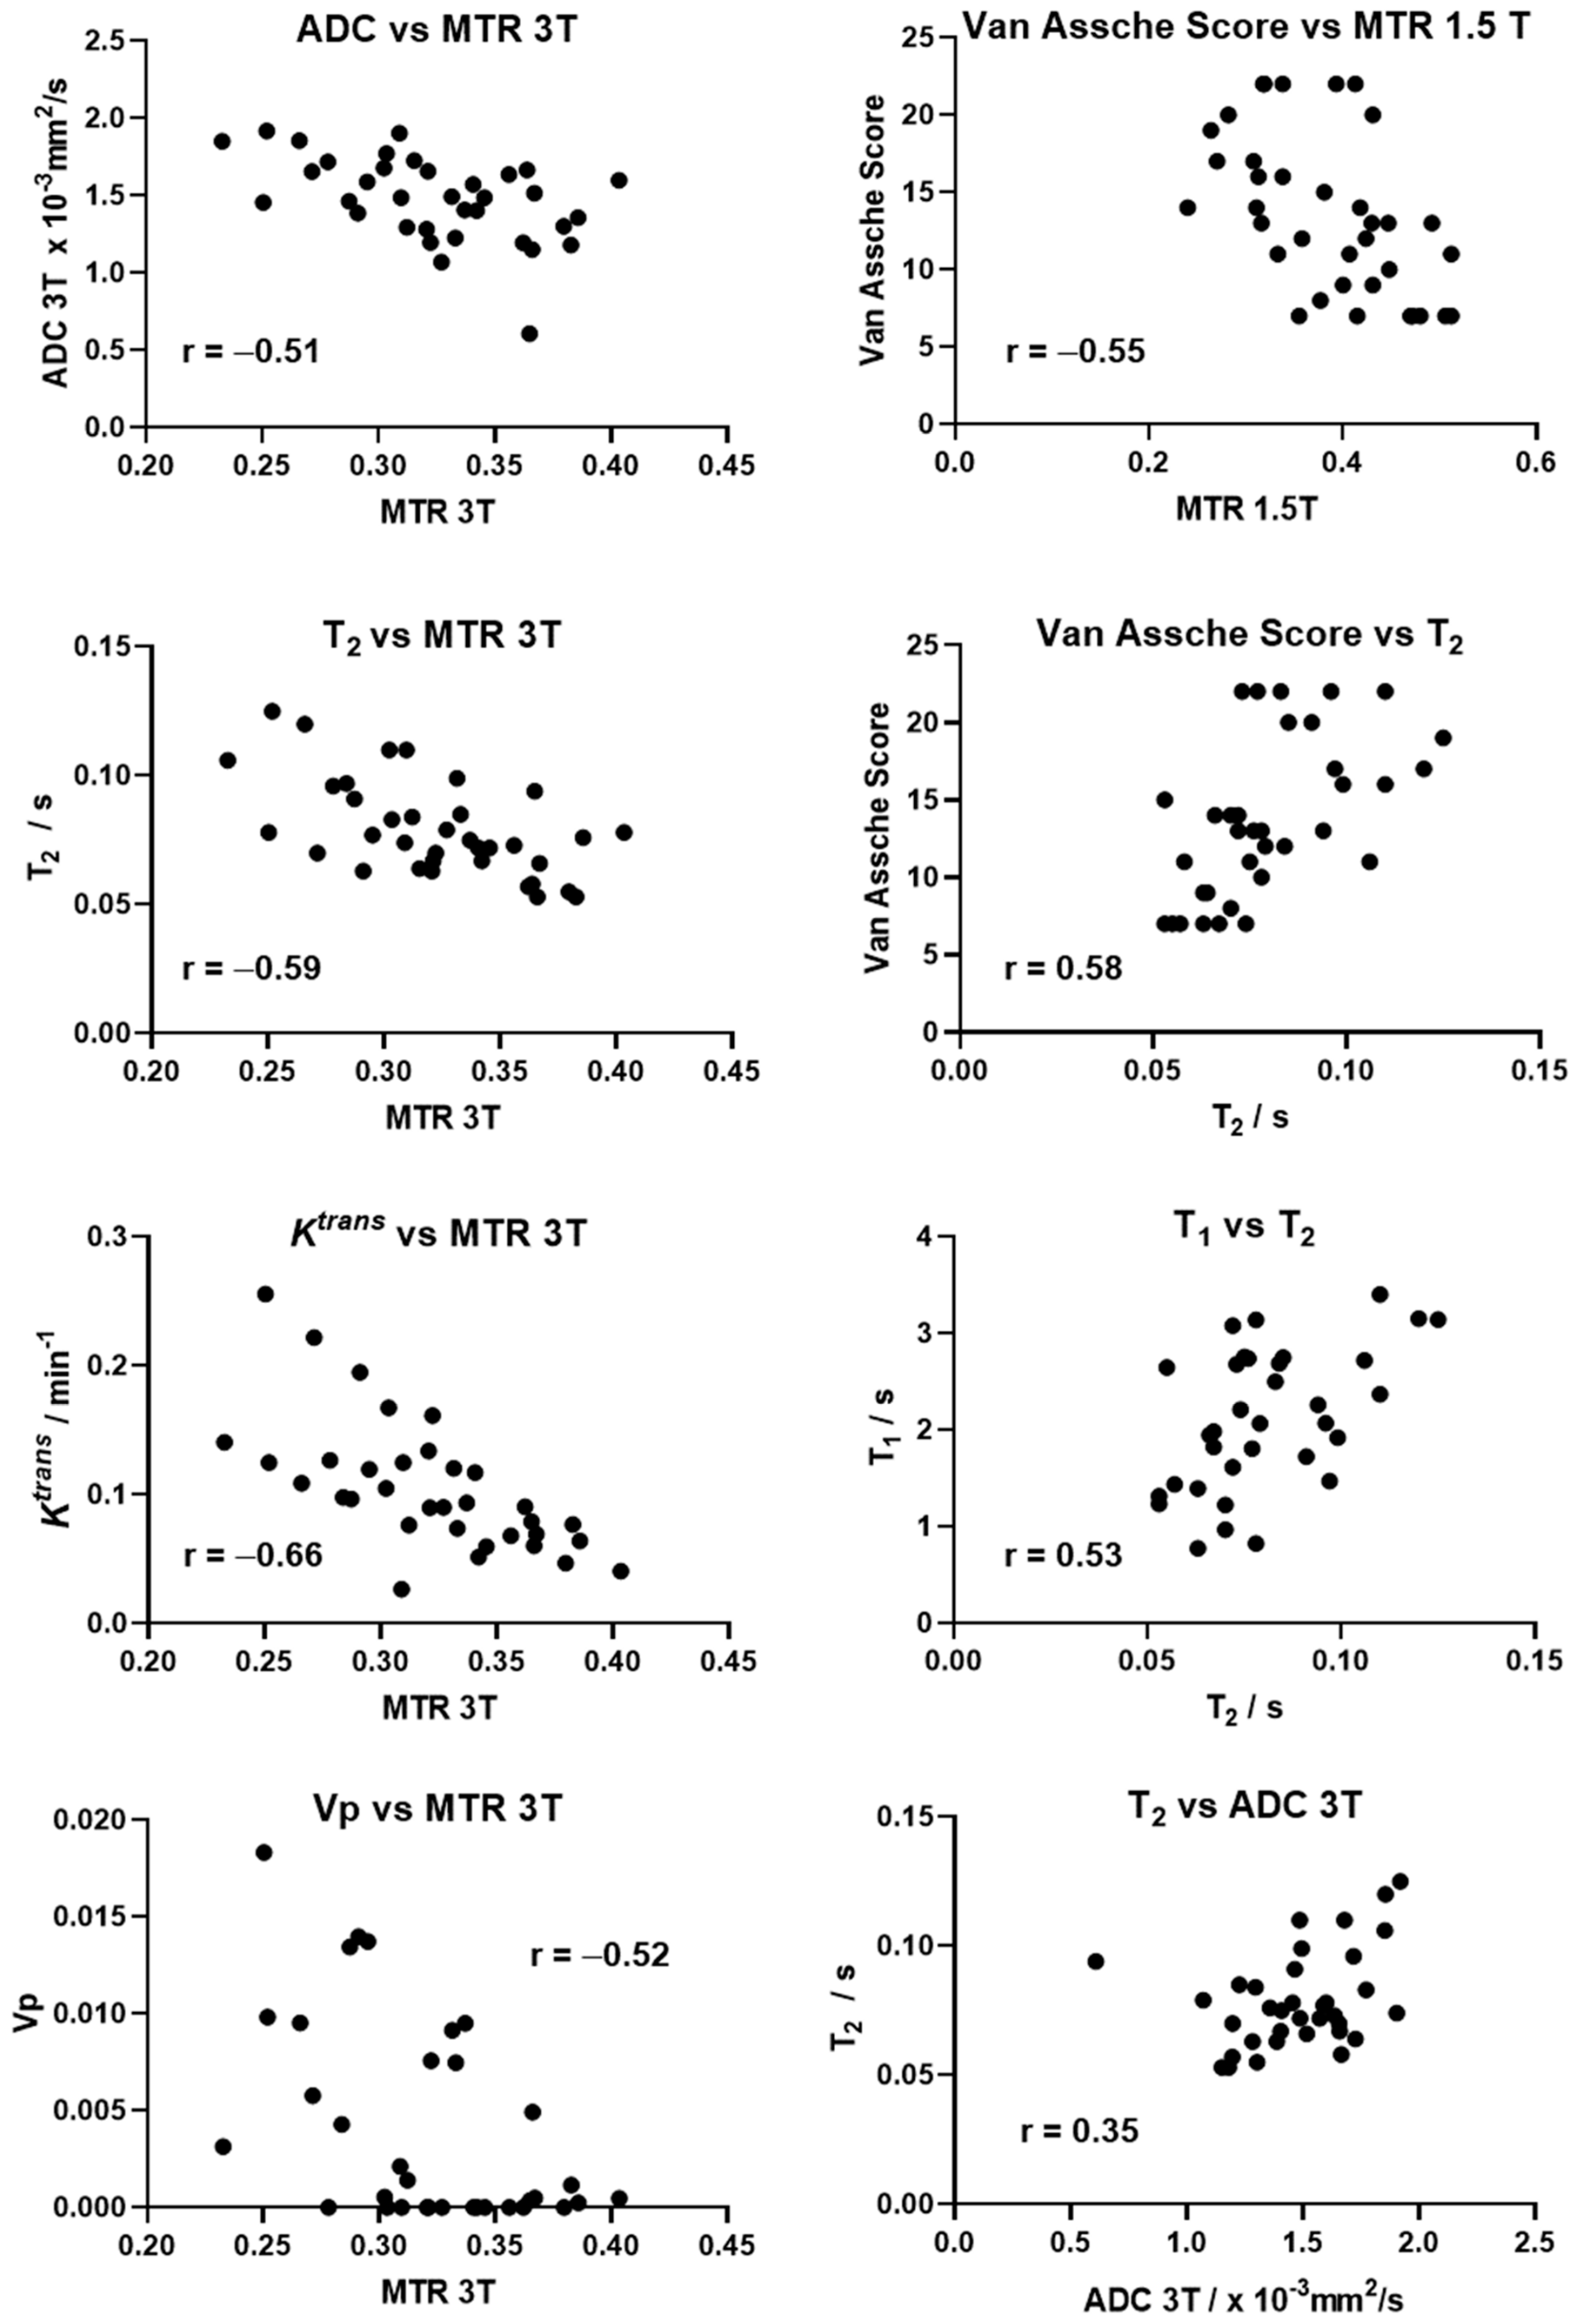

3.5. Correlation between MRI Parameters